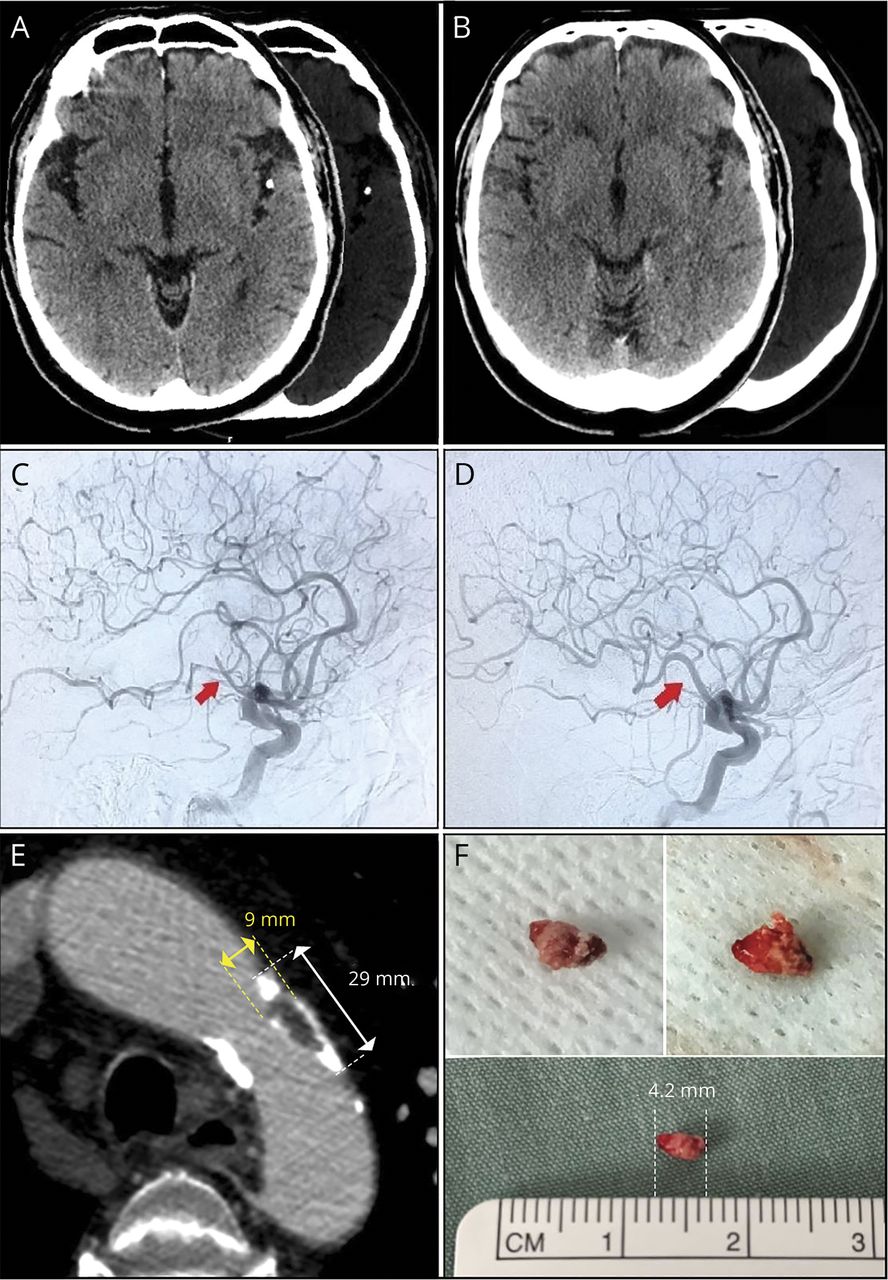

头部的CT显示微妙hypodensity涉及左后部的孤立的丝带,阿尔伯塔省行程计划9的早期CT评分,和一个点状的hyperdensity(最大531 Hounsfield单位密度)在同一侧的希氏裂出现,符合钙化脑栓子(CCE) (图,一个)。还有最近(≤2周)可能涉及左脑桥梗死。头和supra-aortic血管CT血管造影显示29日×9毫米柔软和钙化(443 - 1261年Hounsfield单位)主动脉弓粥样硬化斑块(图E)和右颈内动脉狭窄70%,轻度左颈内nonstenotic斑块,闭塞的左大脑中动脉(MCA)在其mid-distal M2分。多相动脉图像,有衰减的左侧大脑中动脉近端血栓石灰质的组件,延迟冲刷,多相CT血管造影术抵押品的3。灌注成像显示出大面积的潜在可逆缺血在左边MCA领土的后部(图S1,可以从森林女神,doi.org/10.5061/dryad.sqv9s4n1j)。

(一)钙化脑栓子的M2段左大脑中动脉。(B) 24小时的头随访41断层扫描(大脑和骨骼windows):解决钙化脑栓子。(C)脑血管造影:左大脑中动脉闭塞M2段之前机械血栓切除术。(D)脑血管造影:解决左大脑中动脉闭塞。主动脉弓(E) CT血管造影:主动脉弓斑块测量9×29毫米显示了混合软和钙化组件。检索(F)脑钙化栓子测量4.2毫米2过后显示视图的不同表面的不规则和锋利的石灰质的表面。

我们考虑使用IV组织纤溶酶原激活物(tPA),但鉴于可能涉及左桥的亚急性梗死区域(图S2,可以从森林女神,doi.org/10.5061/dryad.sqv9s4n1j)匹配的持续眩晕,我们决定省略第四。CT血管造影后的右臂无力恶化完成后,导致署7。在临床恶化的背景下,大量灌注不匹配,我们决定尝试一个机械血栓切除术(MT)尽管证据支持的低水平的功效M2与M1的过程或终端颈内动脉遮挡。1尽管径向访问是一个合理的选择考虑到主动脉弓斑块,团队决定是安全的追求太过右股动脉。时间从症状出现腹股沟穿刺是40小时。一个诊断脑血管造影术证实M2 / M3结在左侧大脑中动脉闭塞(图中,C)。我们选择直接愿望一传技术(适应)基于血栓的石灰质的组件。2通过半影3后马克斯和6 f索非亚+导管,我们实现了脑梗死的溶栓(TICI) 3分(图D在症状发作后3小时40分。

在后续的头上太CT扫描在24小时后,我们确认CCE的分辨率(图B)。大脑的磁共振成像表现在入院11天,几乎令人眼花缭乱的综合症发病4周后显示一个小进化梗塞轻度出血性转换在左颞叶并没有证据表明桥的梗塞。心电图显示窦性心律和纵波终端力量V1 *女士9019 mV。的超声心动图表现轻度左和右心房扩大,左心室容积指数为41.5毫升/ m2。住院遥测心脏监测是不起眼的,14天门诊扩展心电图监测没有显示心房纤颤。氨基端pro-brain利钠肽(NTpro-BNP) 575 ng / L。